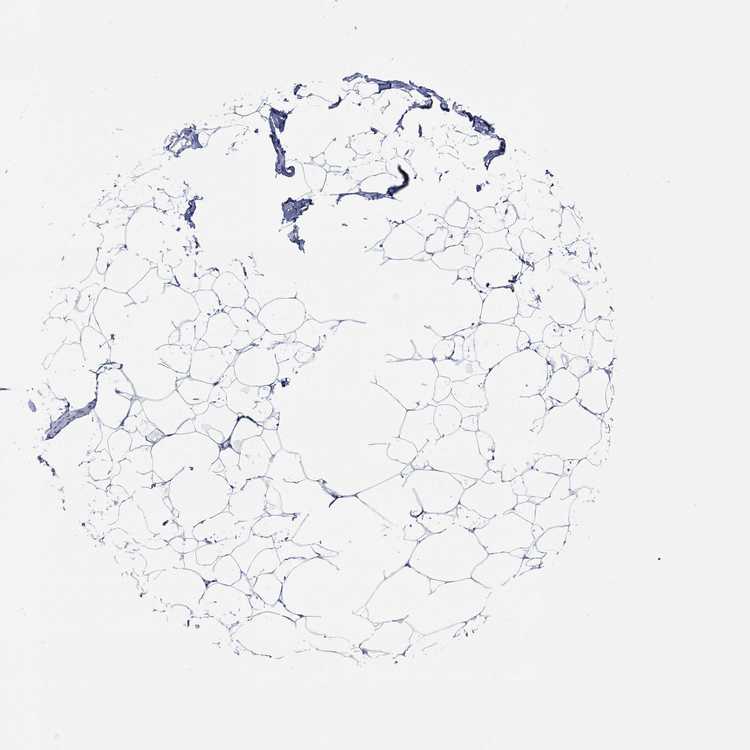

BREAST - Antibody stainingi

Antibody staining in the annotated cell types in the current human tissue is reported as not detected, low, medium, or high, based on conventional immunohistochemistry profiling in selected tissues. This score is based on the combination of the staining intensity and fraction of stained cells.

Each image is clickable and will lead to virtual microscopy that enables deeper exploration of all samples and also displays staining intensity scores, fraction scores and subcellular localization as well as patient and tissue information for each sample.

Antibody HPA023623Antibody HPA066431

Adipocytes Not detectedNot detected

Glandular cells HighNot detected

Myoepithelial cells HighNot detected